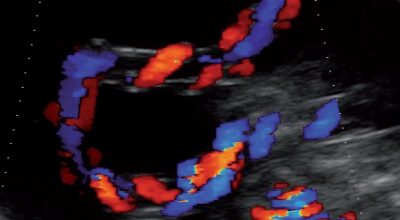

La evolución del feto a través de ecografías

Ecografía con 25 semanas: en esta ecografía, se visualiza las diferentes estructuras del cerebro, y también se analizan las arterias cerebrales (coloreadas).